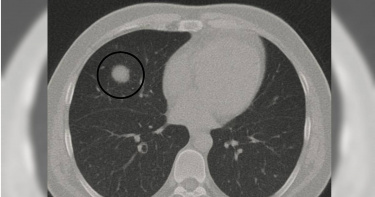

「肺結節」是早期癌症警訊?名醫舉2病例:每年篩檢是關鍵

「肺結節」是早期癌症的警訊?營養功能醫學專家劉博仁分享2個病例解釋,1位因發炎造成的假性結節而免於開刀,另一位則及早發現第一期肺腺癌並成功切除。他提醒大眾,肺結節可能是暫時發炎也可能是癌症警訊,低劑量電腦斷層是重要篩檢工具,並強調飲食、生活習慣與及早追蹤,對維護肺部健康的重要性。營養功能學名醫劉博仁今(2日)在臉書粉專發文分享2個真實病例,提醒大眾面對肺部結節時應保持警覺,但也不要過度恐慌。首先,第一位病患在醫院進行低劑量電腦斷層(LDCT)檢查時,發現肺部有一個1.2公分的不規則結節。對此,劉博仁醫師強烈建議立即開刀,但病患猶豫不決,最後選擇先以功能醫學調理並密切追蹤。4個月後再檢查,結節縮小到僅剩0.3公分,最終確認只是因感染造成的假性結節,幸運地避免了不必要的肺部手術。另一位病患則是女性,右上肺發現0.9公分的毛玻璃樣結節。起初半年間形狀沒有變化,但隨後逐漸長大。劉博仁醫師強烈建議手術,病理結果證實為第一期肺腺癌。由於及早發現與處理,成功切除且沒有擴散,病患因此保住了健康。劉博仁醫師指出,這2個截然不同的結果提醒人們,部分肺結節可能只是暫時性的發炎反應,但也可能是早期癌症的警訊。近年來肺腺癌在華人女性族群中逐漸增加,即使從未吸菸者也可能罹病。他指出原因包括空氣污染(特別是 PM2.5)、二手菸與廚房油煙暴露、基因體質差異(華人女性帶有EGFR基因突變比例較高)、以及慢性發炎反應等。劉博仁醫師強調,LDCT是目前最有效的早期肺癌篩檢工具,能夠發現小於1公分的結節,遠優於傳統胸部X光。醫師會根據國際Fleischner指南與臨床經驗來判斷是否需要手術,若結節大於8毫米且形狀不規則、毛玻璃樣結節持續增大、出現明顯實性成分,或病患屬於高危險族群,就應積極處理,以免錯過治療時機。在日常生活中,雖然無法百分之百預防肺癌,但劉博仁醫師強調,仍可透過習慣與飲食來降低風險,包括避免菸害與二手菸、保持廚房通風、使用空氣清淨機降低PM2.5;飲食上則建議多攝取十字花科蔬菜、番茄、莓果、深海魚類與堅果,並適度補充維生素D、N-乙醯半胱氨酸(NAC)、薑黃素等營養素。保持良好作息、充足睡眠、規律運動與壓力管理,也有助於提升免疫力與肺部健康。他提醒,肺結節不等於肺癌,但也不能掉以輕心。尤其是50歲以上、有吸菸史或家族史的人,每年應進行一次LDCT篩檢。並且要理性判斷,並非所有結節都需要馬上手術,但若出現「增大、變實心、形狀不規則」等變化,就應果斷處理。同時,他也鼓勵大家積極從飲食與生活方式著手,主動守護肺部健康。